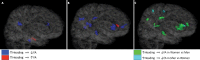

Purpose To examine the role of sex in abnormal white matter microstructure after soccer heading as identified by using the diffusion-tensor imaging (DTI) metric fractional anisotropy (FA). Materials and Methods In this prospective cross-sectional study, 98 individuals who were enrolled in a larger prospective study of amateur soccer players (from 2013 to 2016) were matched 1:1 for age and history of soccer heading in the prior 12 months. Among the subjects, 49 men (mean age, 25.7 years; range, 18-50 years) and 49 women (mean age, 25.8 years; range, 18-50 years) with median total soccer headings per year of 487 and 469, respectively, underwent 3.0-T DTI. Images were registered to the Johns Hopkins University template. A voxelwise linear regression was fitted for FA with terms for the number of headings during the previous 12 months and its interaction with sex after controlling for the following potential confounders: age, years of education, number of lifetime concussions, and handedness. In the resulting statistical maps, P < .01 indicated a statistically significant difference, with a threshold cluster size larger than 100 mm3. Results Among men, three regions were identified in which greater heading exposure was associated with lower FA; eight such regions were identified among women (>100 contiguous voxels, P < .01). In seven of the eight regions identified in women, the association between heading and FA was stronger in women than in men. There was no significant difference of heading with FA between the sexes for any region in which heading was associated with FA among men (P > .01, <100 contiguous voxels). Conclusion With similar exposure to heading, women exhibit more widespread evidence of microstructural white matter alteration than do men, suggesting preliminary support for a biologic divergence of brain response to repetitive trauma. © RSNA, 2018 Online supplemental material is available for this article.